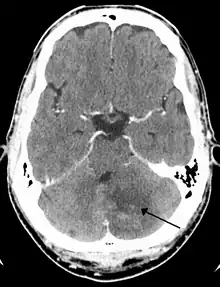

Cerebellar strokes account for only 2-3% of the 600,000 strokes that occur each year in the United States.[3] They are far less common than strokes which occur in the cerebral hemispheres. In recent years mortality rates have decreased due to advancements in health care which include earlier diagnosis through MRI and CT scanning.[4] Advancements have also been made which allow earlier management for common complications of cerebellar stroke such as brainstem compression and hydrocephalus.[4]